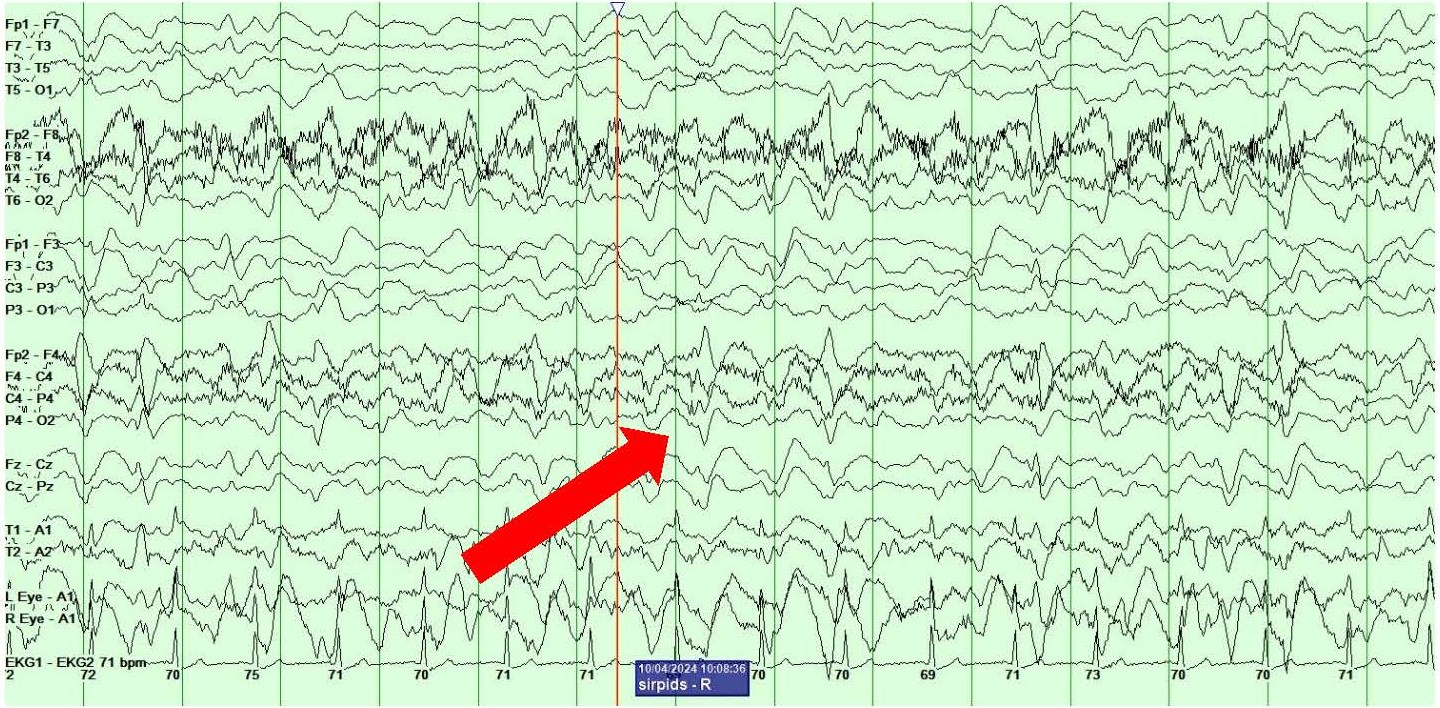

She also showed the presence of right hemispheric LPDs at 1-2 Hz and LRDA at 2-3 Hz that lasted for 1-10 minutes and occurred consistently with stimulation during physical manipulation or care by the medical providers and nursing staff (Figures 4A and 4B). These findings occurred independent of the previously described left hemispheric onset seizures mentioned above. They were felt to represent SIRPIDs (SI-LPDs and SI-LRDA).

Figures 4. A, B) Screenshots from Video EEG showing RIGHT hemispheric SIRPIDs provoked by stimulation (SI-LRDA and SI-LPDs) (marked by red arrows).